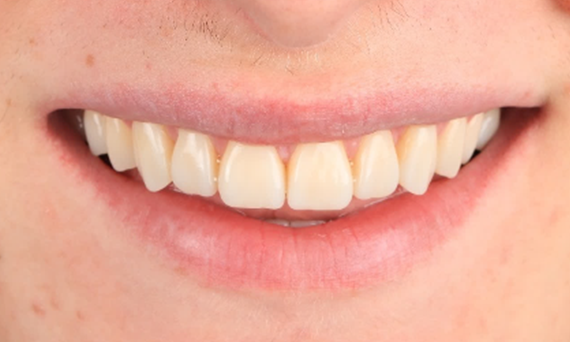

Minimal Preparation Veneers after Trauma of Upper Central Incisors

Restoration with a highly esthetic material in one day after trauma to the maxillary central incisors.

Before: Clinical Situation pre-op. Trauma of upper central incisors

After: Adhesively bonded restorations.